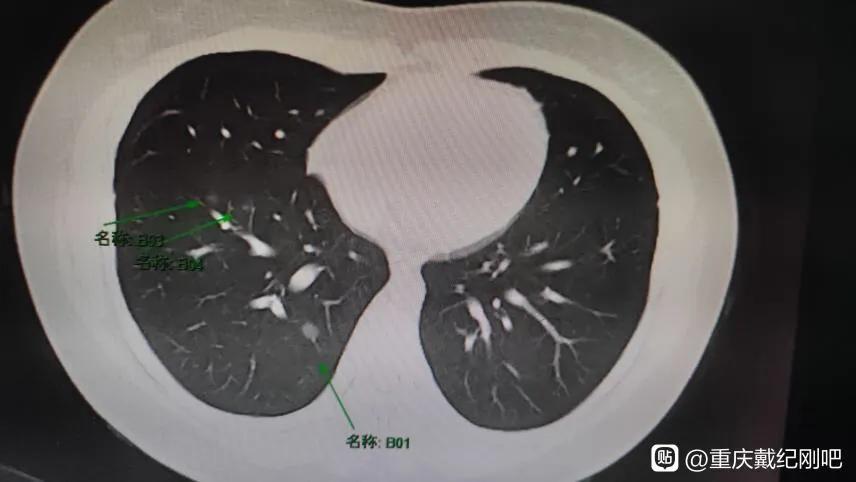

今天的这位也是这样,一个23岁,还在享受人生最好时光的小姑娘,因为长时间咳嗽就诊,查出双肺多发磨玻璃结节,最大的一个结节是9mm×6mm。小姑娘非常棒,不乱于心,不畏将来。自己已经茫然无措了,还可以很坚强的安慰着父母,然后独自面对所有压力。

戴主任你好,我今年才23岁,能不能请您帮帮我,我感觉自己人生还没开始。今年7月28号,因为持续几月间断刺激性咳嗽去我们市医院就诊,查出来双肺散在多发磨玻璃结节,最大的0.8cm。结果出来我就天塌了,市医院建议我入院治疗。然后就开始整夜睡不着,大半夜起来哭,我真的太害怕了。后面去了四川省肿瘤医院看了医生,那边看到片子说,先口服拜复乐两周,一月以后复查CT。

然后9月2号做了增强CT,多发磨玻璃结节,右下叶磨玻璃结节0.9x0.6cm。医生看了报告说性质不定,很危险。听到我真的茫然无措,不知道怎么办了,开始不停百度,每天都休息不好,有时半夜还起来坐着发呆。从知道戴主任开始就一直一直没抢到号,最开始我还能安慰自己下一次,可是时间越长我越心慌。大家帮帮我吧,我想能不能去主任那里加号看一下。一边我还一直安慰我爸妈,一边自己一个人承受这些,做什么都是自己跑,真的好难受啊。另外很感谢热心的小哥教我怎样拍CT图,怎样贴吧发帖发图片。